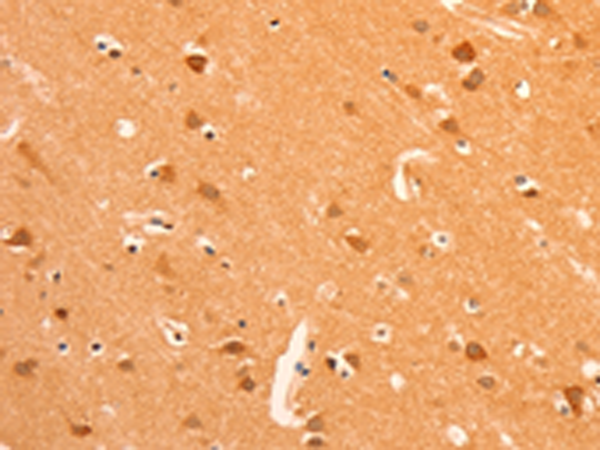

IHC positive control: |

Human brain |